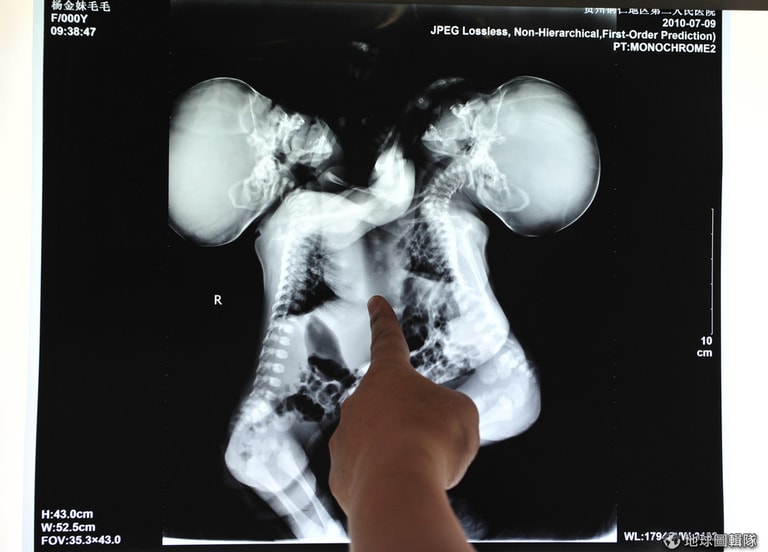

2010年7月的中國,醫療團隊正在針對一對連體姊妹的X光片進行討論,看她們是否適合進行分離手術。

路透社肚臍以下相連的姊妹

瑪莉亞和孔索拉達(Maria and Consolata Mwakikuti)出生後肚臍以下的部位就是相連的,她們共享著肝和肺,並各自擁有獨立運作的心臟、頭、手臂。過去在接受訪問時,兩人均表達出不想透過手術分離的想法。